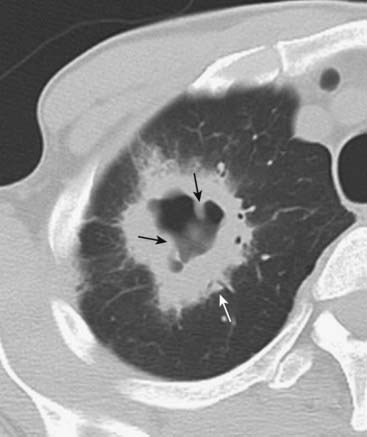

Centriacinar (centrilobular) emphysema features focal destruction limited to the respiratory bronchioles and the central portions of acinus. It is associated with cigarette smoking and is most severe in the upper lobes (Fig. 12-22A).

Panacinar emphysema involves the entire alveolus distal to the terminal bronchiole. It is most severe in the lower lung zones and generally develops in patients with homozygous alpha 1-antitrypsin deficiency (Fig. 12-22B).

Paraseptal emphysema is the least common form. It involves distal airway structures, alveolar ducts, and sacs. Localized to fibrous septa or to the pleura, it can lead to formation of bullae, which may cause pneumothorax. It is not associated with airflow obstruction (Fig. 12-22C).

Figure 12-22 Types of emphysema.

A, Centriacinar (centrilobular) emphysema features focal destruction limited to the respiratory bronchioles and the central portions of the acinus (solid white arrows). It is associated with cigarette smoking and is most severe in the upper lobes. B, Panacinar (panlobular) emphysema involves the entire alveolus distal to the terminal bronchiole, is most severe in the lower lung zones, and generally develops in patients with homozygous alpha1-antitrypsin deficiency. C, Paraseptal emphysema is the least common form, involves distal airway structures, alveolar ducts, and sacs, tends to be subpleural, and may cause pneumothorax.